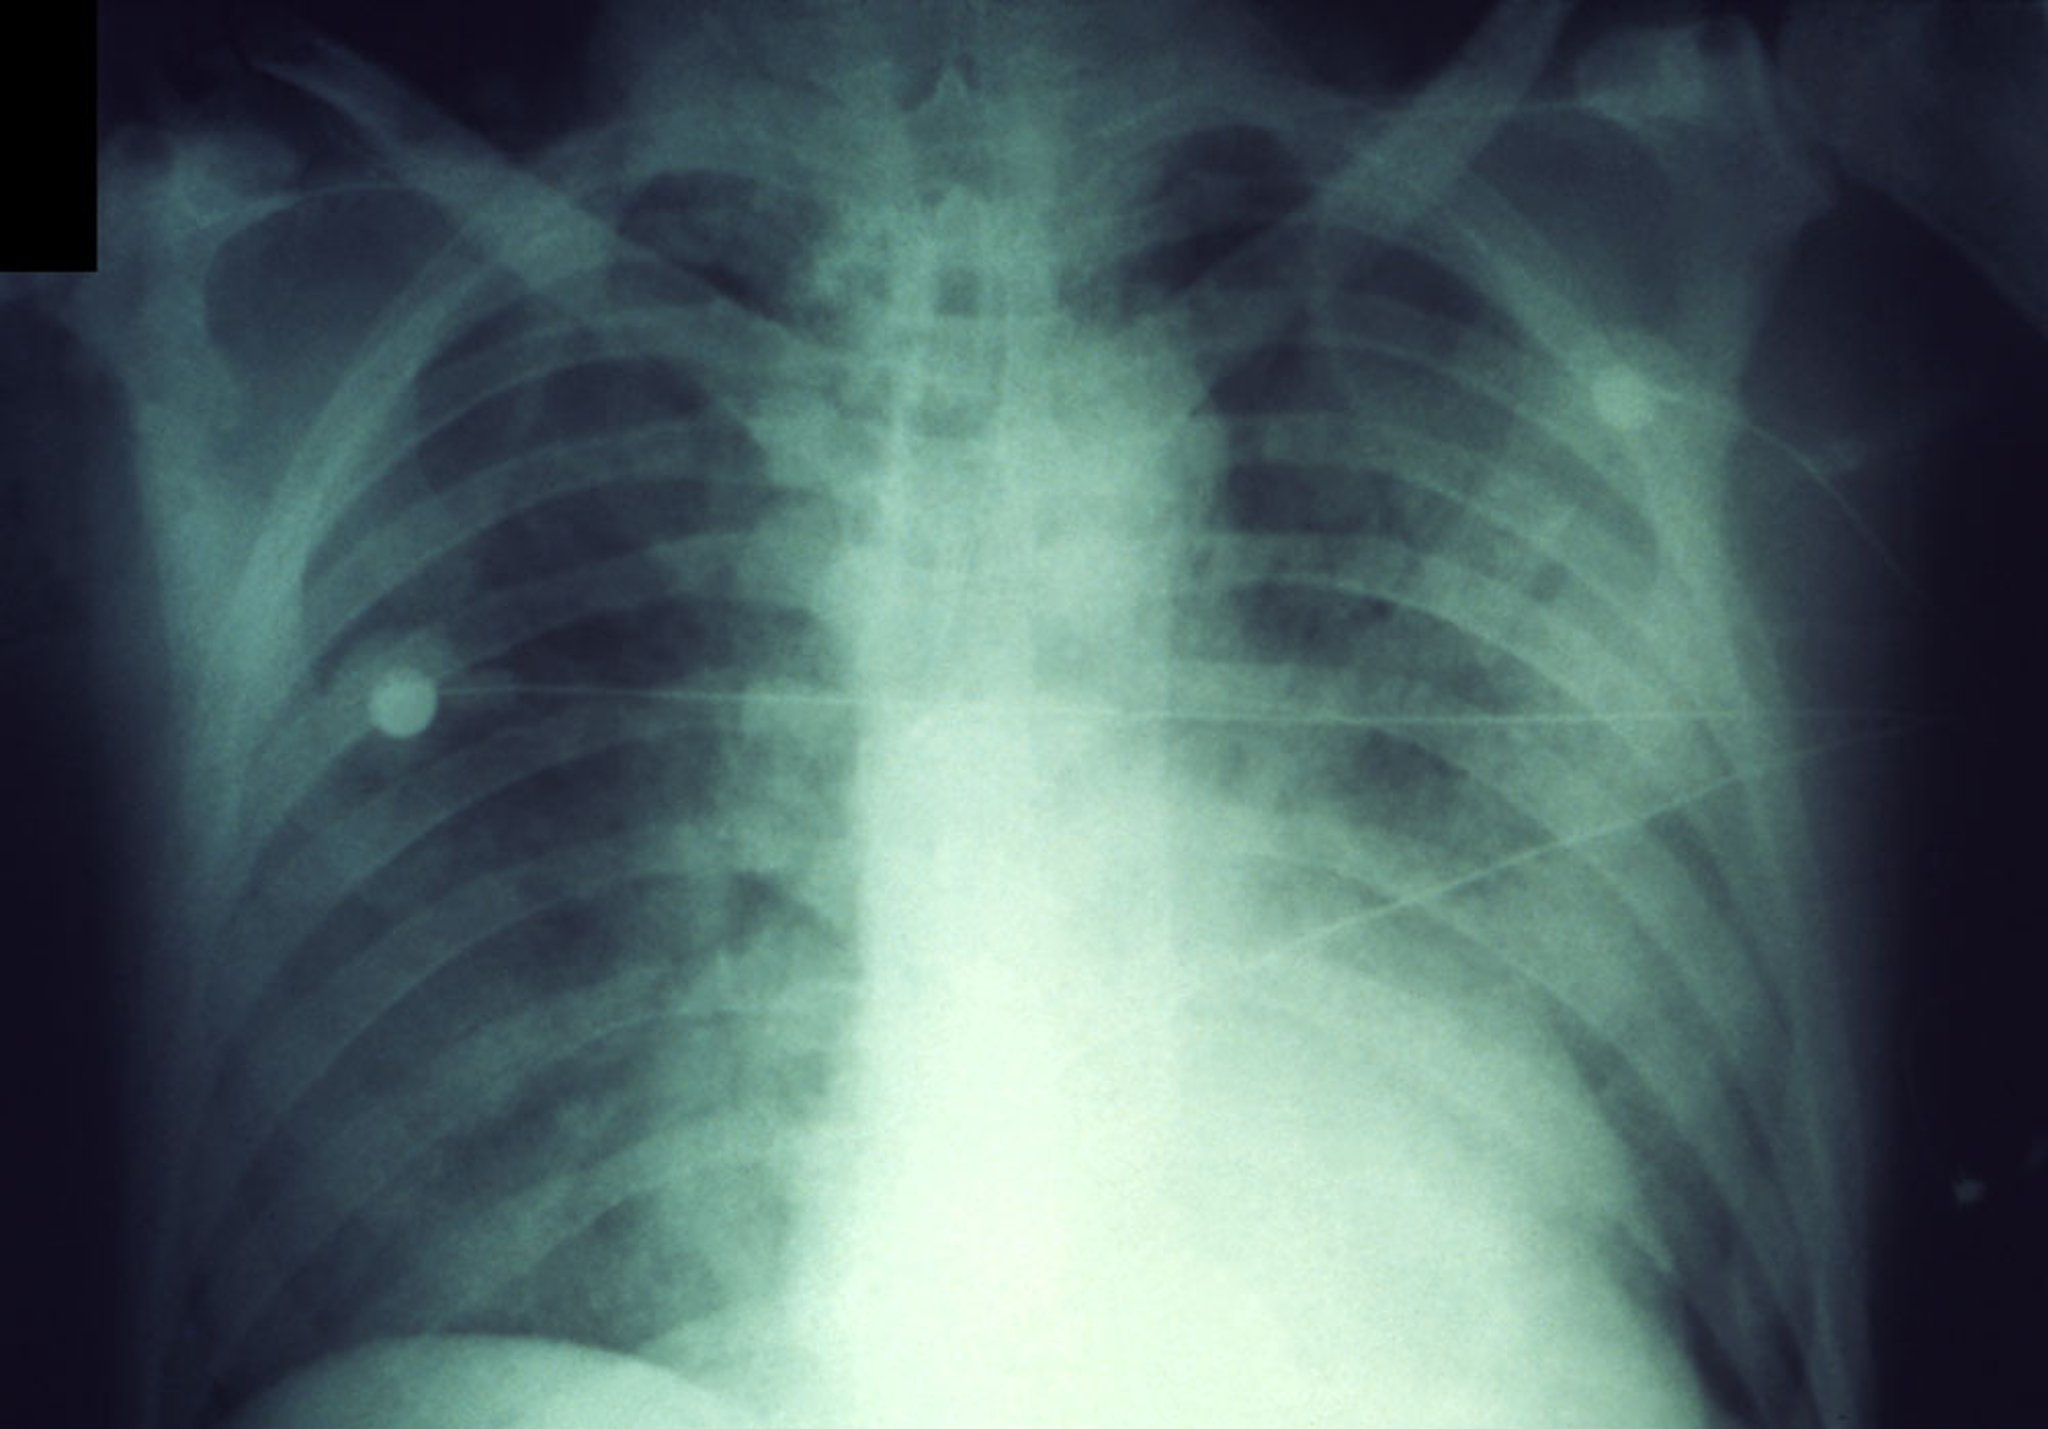

Essa radiografia de tórax mostra infiltrados rapidamente progressivos na peste pneumônica.

CDC/Dr. Jack Poland

Pacientes com sintomas ou sinais pulmonares devem realizar radiografia de tórax, que mostra pneumonia rapidamente progressiva em peste pneumônica. A contagem de leucócitos geralmente é de 10.000 a 20.000/mcL (10 a 20 × 109/L), com numerosos neutrófilos imaturos.

Inicialmente, radiografias de tórax mostram pneumonia lobar seguida de consolidação densa e disseminação broncopneumônica para outras áreas do mesmo pulmão ou do pulmão oposto.